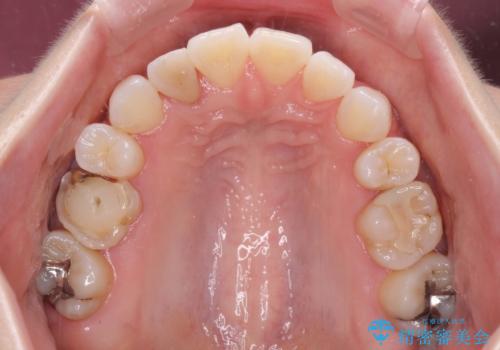

変色した前歯 オーダーメイドタイプのオールセラミッククラウン

- 虫歯により神経を取り除いた前歯の変色が気になるとのことで来院された患者様です。

レントゲン写真より、歯根の炎症が認められなかったため、ファイバーコアによる土台築製後、オーダーメイドタイプのオールセラミッククラウンにて補綴することとしました。